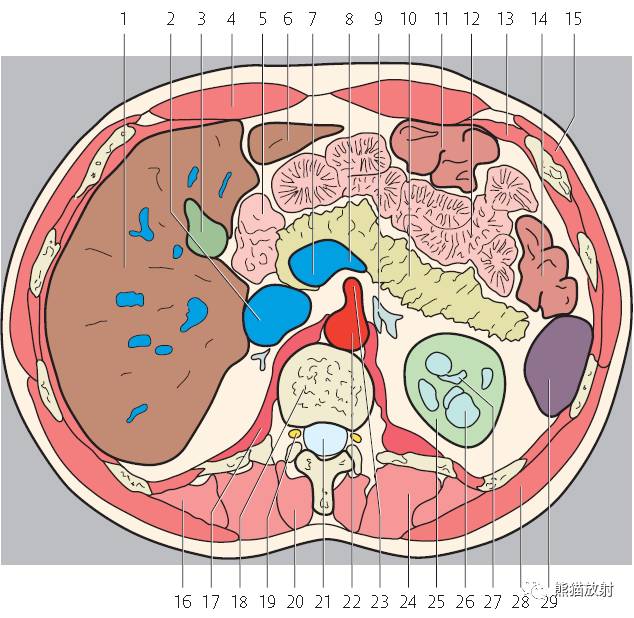

第三层

1、肝右叶;2、肝尾状叶;3、下腔静脉;4、肝门静脉;5、腹直肌;6、肝圆韧带;7、肝左叶;8、十二指肠降段;9、腹白线;10、肠系膜上动脉;11、腹腔干;12、胃;13、脾静脉;14、胰腺;15;空肠;16、横结肠;17、降结肠;18、左结肠静脉;19、腹外斜肌;20、膈肌;21、奇静脉;22、髂肋肌(胸段);23、胸导管;24、胸椎;25、棘肌;26、椎管和脊髓;27、腹主动脉;28、半奇静脉;29、最长肌;30、肾上腺动脉;31、左侧肾上腺;32、左肾;33、左肺;34、背阔肌;35、脾脏;36、肝门区;37、圆韧带凹痕;38、肝十二指肠韧带;39、网膜孔;40、网膜囊/大网膜;41、胰淋巴结;42、右膈下隐窝;43、肝淋巴结;44、腰淋巴结;45、膈上淋巴结;46、后纵隔;47、脾门;48、左结肠旁沟。